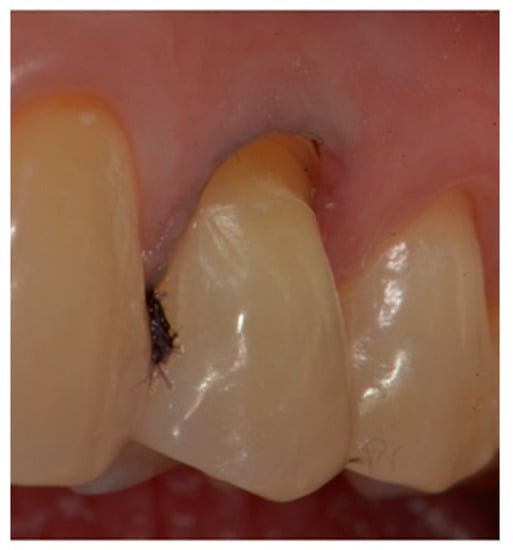

- First refinement of the restoration and removal of the retraction cord (Figure 7).